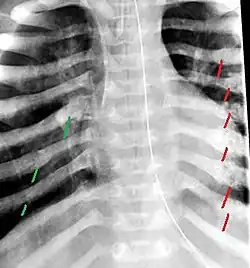

The material factual allegations of the amended complaint are as follows. Plaintiff was born on May 14, 1970. On repeated occasions during the first year of her life she was severely beaten by her mother and the latter's common law husband, one Reyes. On April 26, 1971, when the plaintiff was eleven months old, her mother took her to the San Jose Hospital for examination, diagnosis, and treatment. The attending physician was defendant Dr. Flood, acting on his own behalf and as agent of the defendant San Jose Hospital. At the time, the plaintiff was suffering from a comminuted spiral fracture of the right tibia and fibula, which gave the appearance of having been caused by a twisting force. Plaintiff's mother had no explanation for this injury. Plaintiff had bruises over her entire body. In addition, she had a non-depressed linear skull fracture which was then in the process of healing. Plaintiff demonstrated fear and apprehension when approached. Inasmuch as all plaintiff's injuries gave the appearance of having been intentionally inflicted by other persons, she exhibited the medical condition known as the battered child syndrome.

The complaint avers that as a proximate result of the foregoing negligence plaintiff was released from the San Jose Hospital without proper diagnosis and treatment of her battered child syndrome, and was returned to the custody of her mother and Reyes who resumed physically abusing her until she sustained traumatic blows to her right eye and back, puncture wounds over her left lower leg and across her back, severe bites on her face, and second and third degree burns on her left hand.

On July 1, 1971, plaintiff was again brought in for medical care, but to a different doctor and hospital. Her battered child syndrome was immediately diagnosed and reported to local police and juvenile probation authorities, and she was taken into protective custody. Following hospitalization and surgery she was placed with foster parents, and the latter subsequently undertook proceedings to adopt her. Plaintiff's mother and Reyes fled the state, but were apprehended, returned for trial, and convicted of the crime of child abuse.[3]

For example, the leading article by Kempe et al., op. cit., supra,[10] states that "A physician needs to have a high initial level of suspicion of the diagnosis of the battered-child syndrome in instances of subdural hematoma, multiple unexplained fractures at different stages of healing, failure to thrive, when soft tissue swelling or skin bruising are present, or in any other situation where the degree and type of injury is at variance with the history given regarding its occurrence . . . ." (Id., at p. 20.) Of the different types of fractures exhibited, an arm or leg fracture caused by a twisting force is particularly significant because "The extremities are the 'handles' for rough handling" of the child by adults. (Id., at p. 22.) The article also contains numerous recommendations to conduct a "radiologic examination of the entire skeleton" for the purpose of confirming the diagnosis, explaining that "To the informed physician, the bones tell a story the child is too young or too frightened to tell." (Id., at p. 18.) Finally, on the subject of management of the case it is repeatedly emphasized that the physician "should report possible willful trauma to the police department or any special children's protective service that operates in his community" (id., at p. 23) in order to forestall further injury to the child: "All too often, despite the apparent cooperativeness of the parents and their apparent desire to have the child with them, the child returns to his home only to be assaulted again and suffer permanent brain damage or death." (Id., at p. 24.)